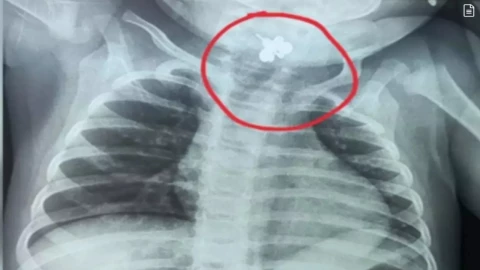

La menor, de apenas diez meses, fue atendida tras cinco días con fiebre constante y rechazo a los alimentos. Ante la falta de mejoría, el equipo médico decidió ampliar los estudios y realizar una radiografía de tórax.

El estudio reveló un cuerpo extraño alojado en la región faringolaríngea. Se trataba de un anillo, cuya ausencia no había sido notada por la familia, ya que probablemente se encontraba al alcance de la bebé en el dormitorio. El hallazgo confirmó que la bebé con un anillo atorado en la garganta había sufrido una broncoaspiración.